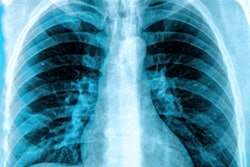

A single radiographer performed the lateral lumbar spine x-rays centered on the L3 vertebra with patients in the left lateral recumbent position. A rheumatologist read all of the scans. Kellgren-Lawrence (K-L) grade-based scores were used to measure radiographic changes in lumbar spine segments, while disk space narrowing and osteophytes were assessed using standard validated methods.